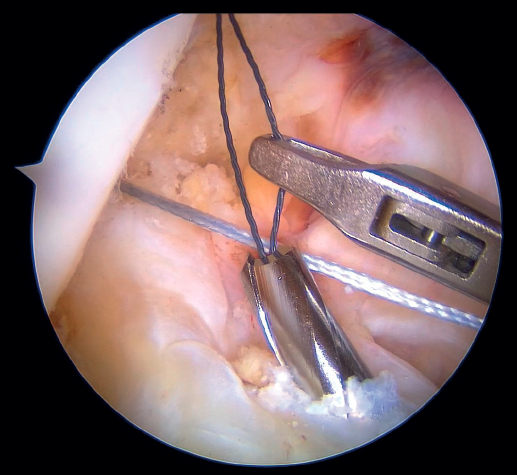

The anteromedial and posterolateral fascicles of the ACL are then identified for suturing separately. Using a suture passer, a closed loop suture is passed through the anteromedial fascicle at its most distal zone, and the loopless extremity is carried alternately (medial to lateral, lateral to medial and so on) to the most proximal zone, usually involving 3 or 4 passes of the suture. The thread may knot on itself during suturing if we are not attentive to it on entry and exit. To solve this problem, we simply undo the knot with retrieval forceps and repeat the step if necessary.

On completion, the thread is retrieved through the accessory anteromedial portal. The process is then repeated, this time with the posterolateral fascicle. To prevent the first thread from breaking with passage of the second thread, it must be ensured that entry and exit in the ligament are very posterior and ideally somewhat proximal to those used for the anteromedial fascicle. Once having reached the most proximal zone after 3 or 4 passes, retrieval is carried out in the same way through the accessory anteromedial portal.